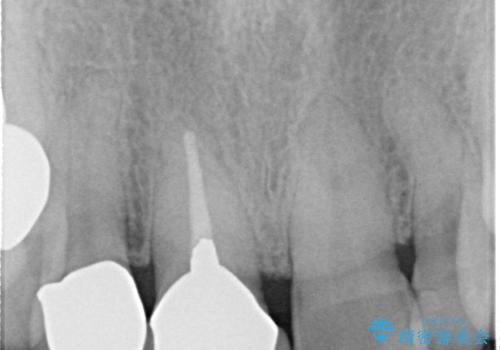

- 矮小歯である前歯がしみるとのことで来院された患者様です。

上顎前歯の歯肉ラインにエナメル質の欠損が認められ、そこが原因で冷たいものがしみている状態でした。

歯の大きさが小さいこと、隣の歯や反対側のセラミッククラウンの境目が見えていることなどから、前歯4本あるいは6本に対して、オールセラミッククラウンによる補綴治療をご提案しました。